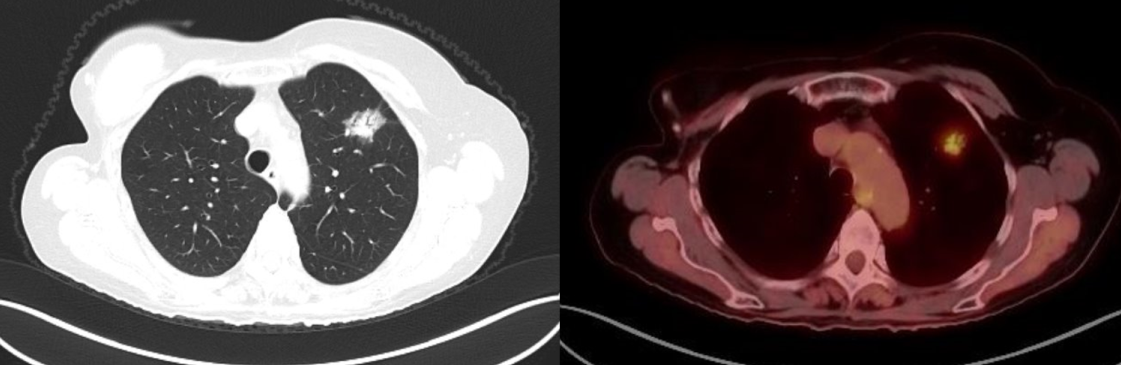

A 70-year-old woman with a past history of breast cancer in 2004 also had a nonperipheral pseudonodular ground glass appearance lesion in the left upper lobe since 2010, a core-needle biopsy in 2012 and 2015, and a diagnosis of benign pneumocytoma (Figure 1). Since 2018, the lesion had a growth of the solid component in chest computed tomography scan, so a positron emission tomography scan was performed, which showed an increased metabolic uptake in the lesion (SUV max 2.77) (Figure 2).

Figure 1